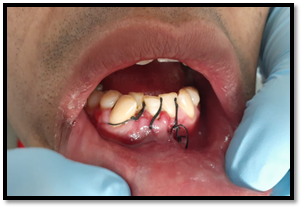

Cirugía propiamente dicha:

Se realizó la osteotomía para el retiro de los dentículos que está formando al odontoma, llegando a la extirpación de 13 dentículos.

Imagen 8. Odontosección.

Imagen 9. Remoción de Odontomas.

Imagen 10. Total de dentículos extraídos .

Se colocó FIBRINA RICA EN PLAQUETAS en la cavidad.

Imagen 11. Colocación de fibrina rica en plaquetas.

Sutura

Vicril 0000, se suturó primero las papilas interdentales, luego la liberatríz. Siendo un numero de 4 puntos simple de sutura.

Imagen 12. Sutura.